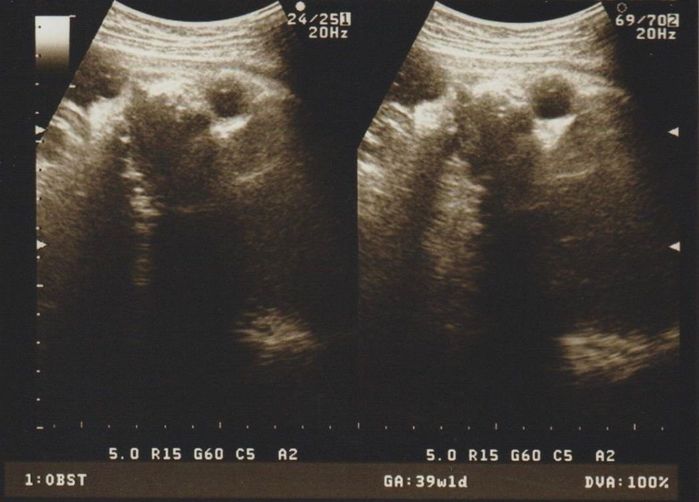

毎日散歩をして、出産の準備を - 妊娠39週目のエコー写真

推定体重2871g 毎日散歩をして、出産の準備を

ここ1週間は毎日30分散歩をして、積極的に動くようにしていました。前回よりさらにおなかも張ってきて、「内診した感じも良い感じになっている」と言われ、「次の検診までには生まれちゃうかな!? 」とドキドキでした。赤ちゃんが3000gを超える前には産みたいと思い、検診から帰宅するとまた散歩に出かけたのでした。